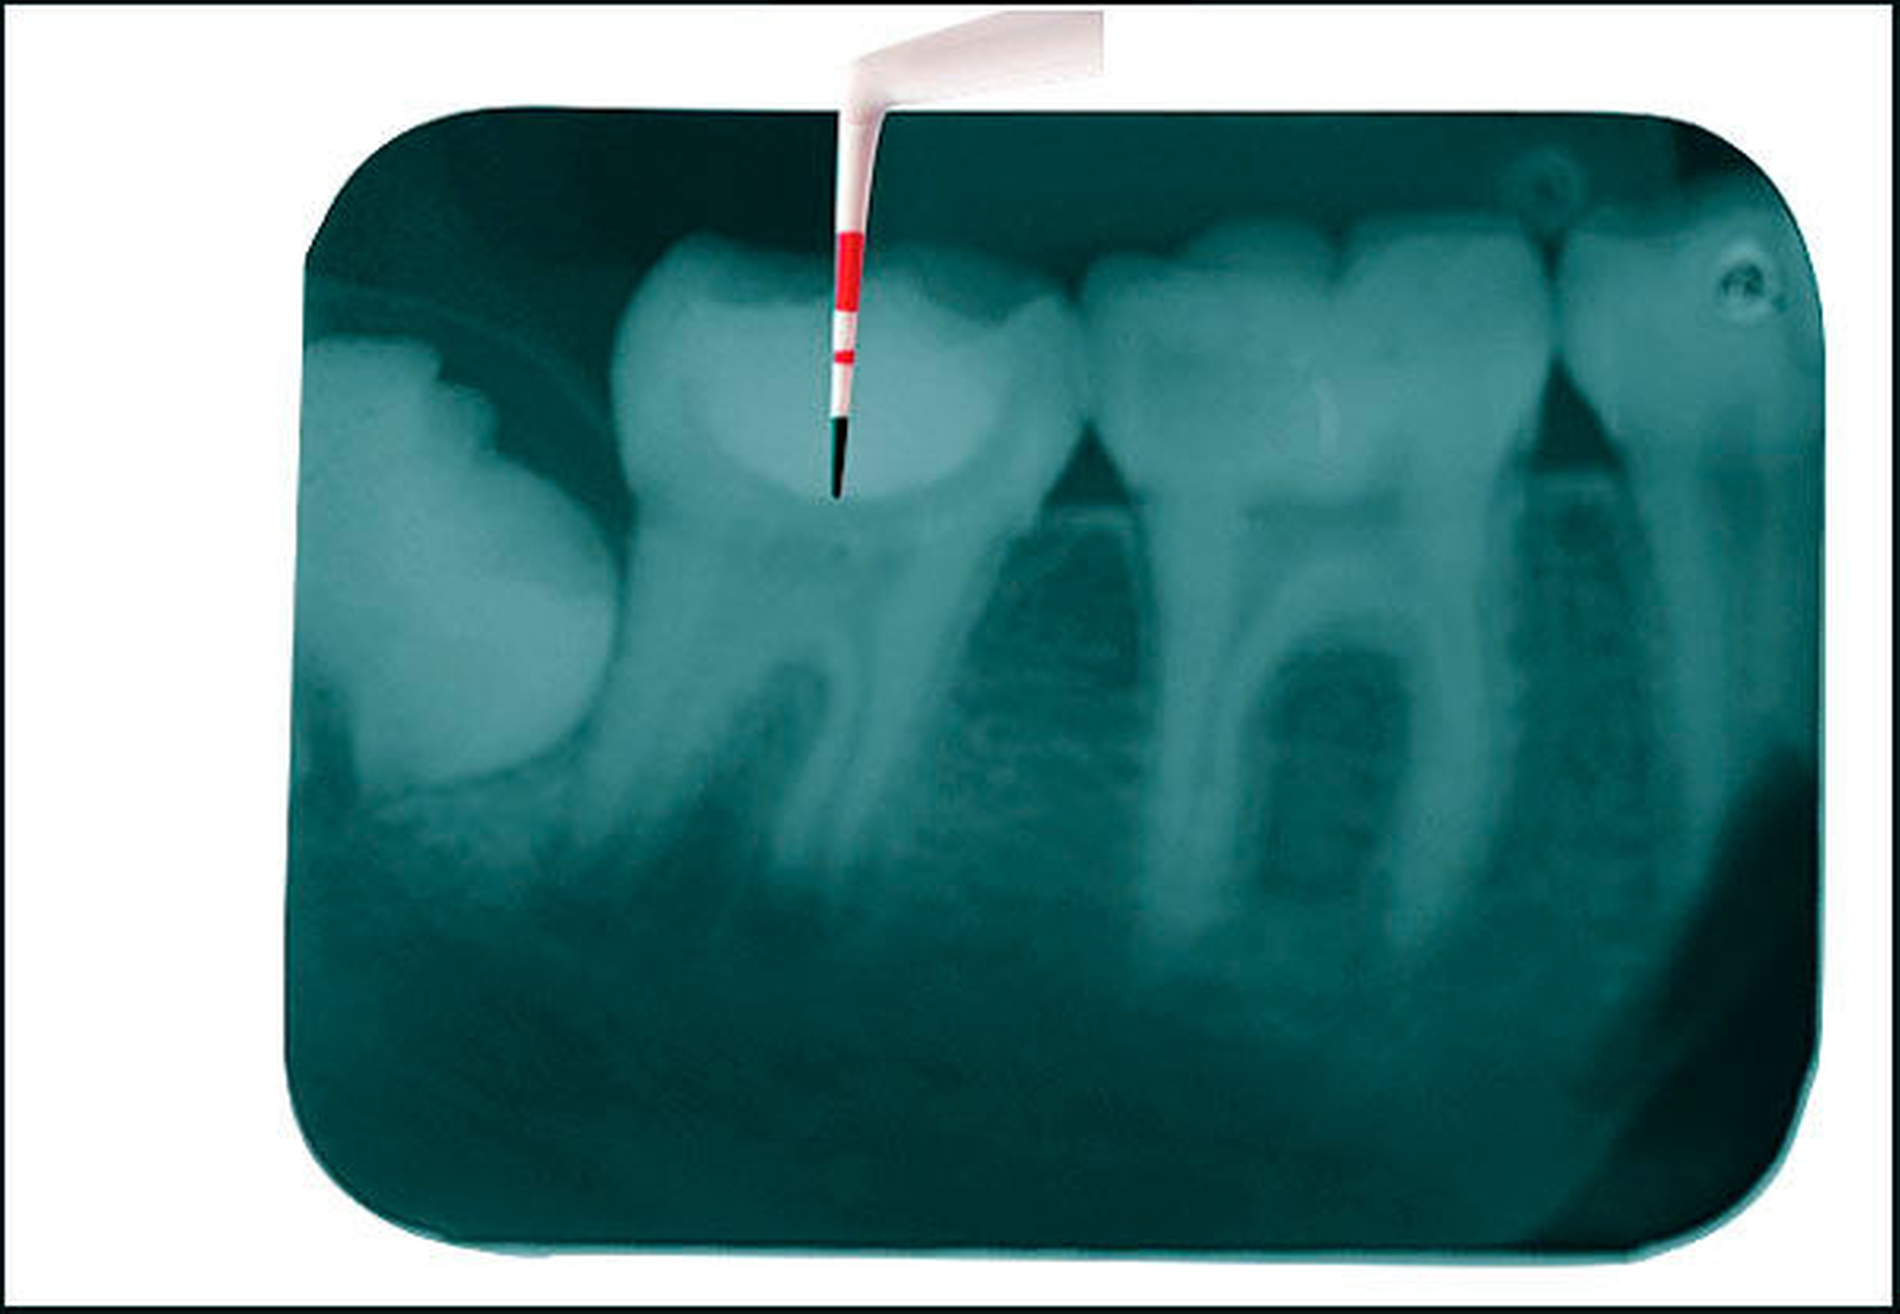

In tiefen Bereichen (meist Approximalkästen) ist der Abstand zur Lichtquelle größer, und weniger Lichtenergie kommt am Komposit an (im Vergleich zu Schichten nahe der Okklusalfläche). Um dies zu kompensieren, sollte die Belichtungszeit erhöht werden.

Nach Entfernung der Matrize sollte die Restauration von bukkaler und von lingualer Seite zusätzlich belichtet werden.